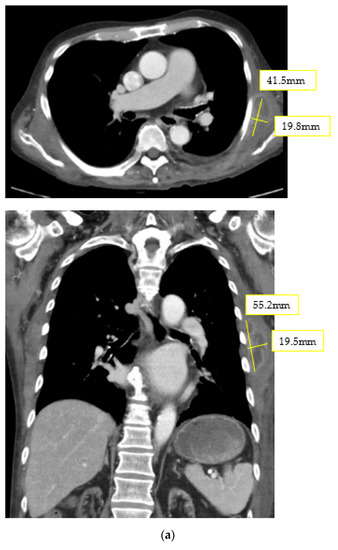

2. Case Report